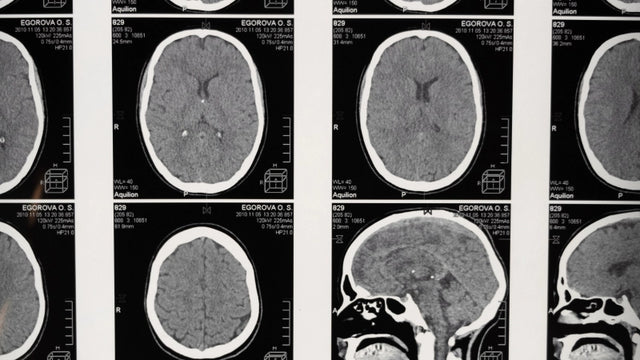

신경 영상 기술은 신경계에 대한 올바른 연구를 멸망시키는 일련의 과정을 가정합니다. 이들은 다양한 병리에서 뇌 병변을 식별하는 데 특히 유용하며, 환자가 매일 발생하는 기능적 결함과 관련된보다 정확하고 상세한 중재 계획을 허용합니다. 이들의 지식과 관리는 건강 분야에서 자신의 작업을 수행하는 모든 전문가에게 필요하지만 신경 과학 연구의 맥락에도 있습니다. 신경 영상 기술 과정을 통해 이러한 기술과 그 적용을 알 수 있습니다. 온라인 방법론과 개인화 된 교육 모니터링 덕분에 교육 및 품질 교육을 받게됩니다.

신경 영상 기술 과정은 구조와 기능 수준에서 신경계 연구에 사용되는 주요 기술과 관련된 지식을 습득 할 수 있도록 준비합니다. 또한, 그것은 뇌 손상으로 인한인지에 영향을 미치는 신경 학적 환자의 임상 연구와 직접 관련된 인간 행동의 신경 생리 학적 염기를 심화시킨다.